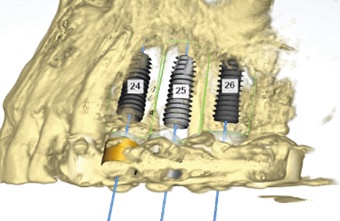

상악동 거상술은 어떤 치료인가요?

상악동 거상술은

상악동 안쪽 막을 조심스럽게 들어 올린 뒤

그 아래 공간에 뼈이식 재료를 채워

임플란트가 들어갈 수 있는 높이를

확보하는 치료입니다.

쉽게 말하면

임플란트를 심기 전에

뼈가 자랄 수 있는 바닥을 만들어주는 과정입니다.

이 치료의 목적은 단순합니다.

임플란트가 잇몸과 뼈에 단단히 자리 잡아

씹는 힘을 안정적으로 견딜 수 있도록

기초를 다지는 것입니다.